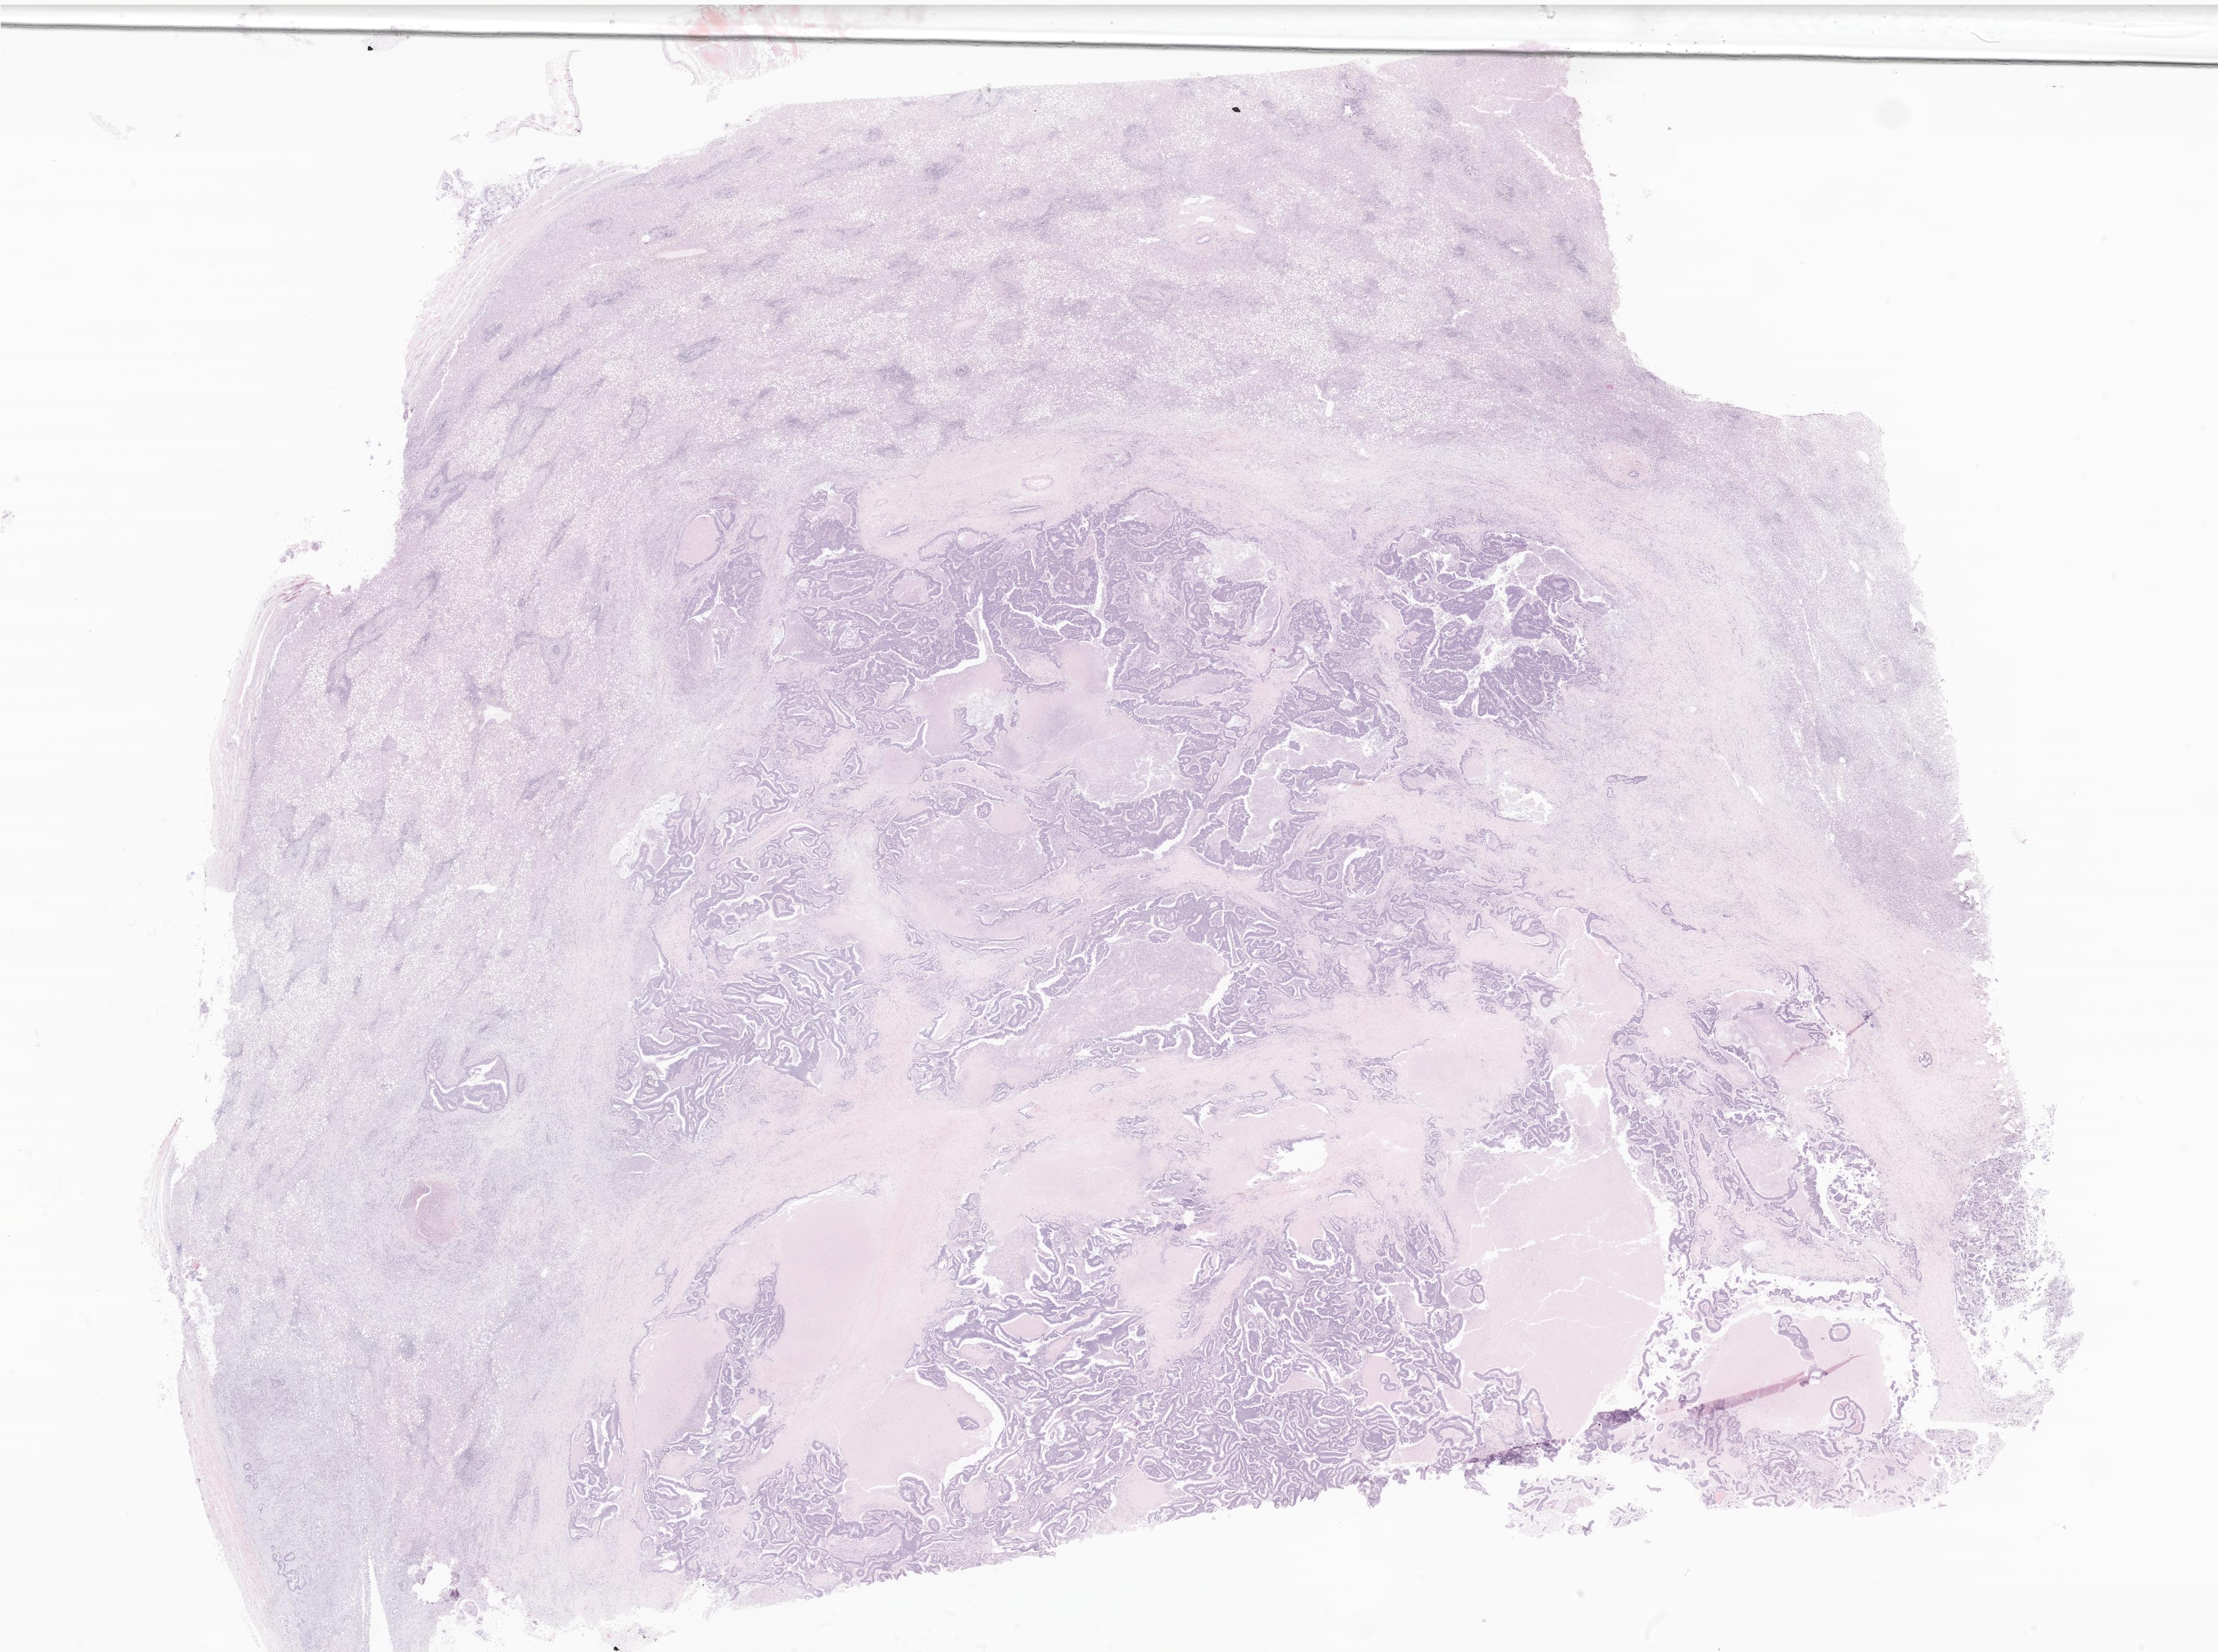

This dataset contains anonymised whole slide images (WSIs) of human liver received during routine clinical practice, comprising a variety of benign and malignant diagnoses. This dataset includes biopsies and surgical resection specimens. Each case includes a liver tumour (either primary or metastatic) along with non-tumour/background liver sampling. All cases include a H&E stain along with any additional histochemical or immunohistochemical stains where available.